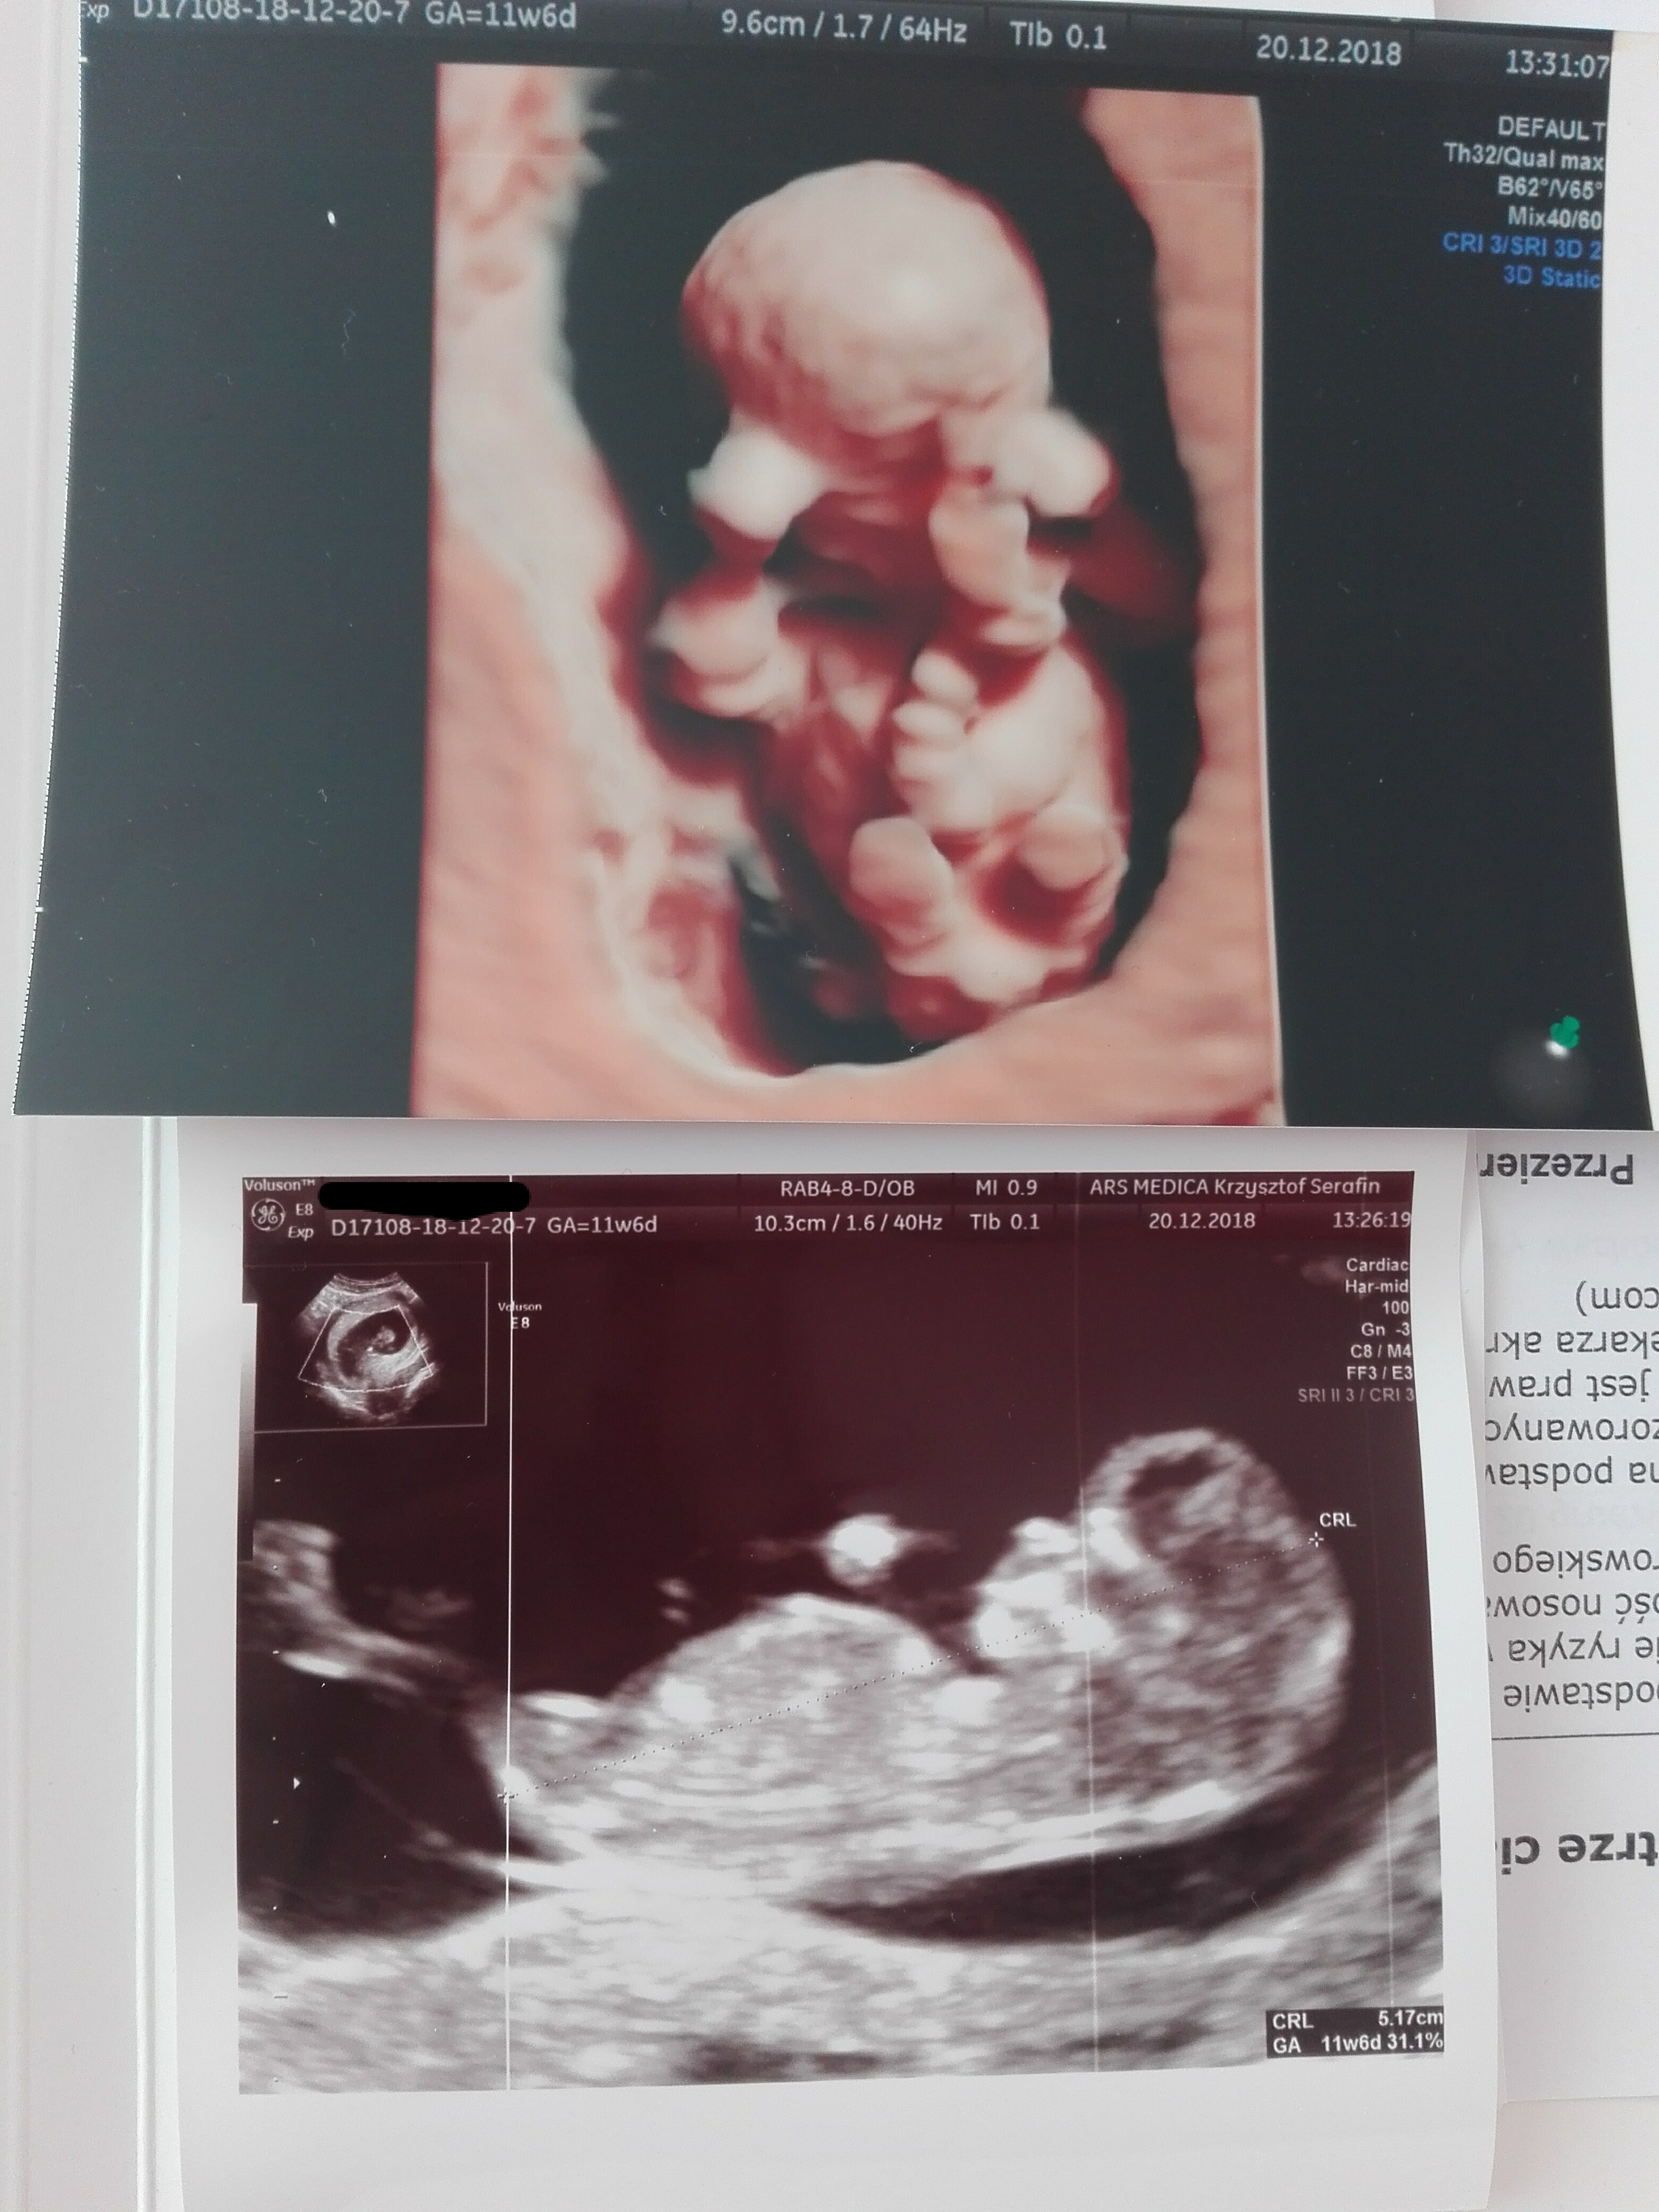

Jakie syrki słodkieDziewczyny, to nasze zdjecia z wczoraj <3Zobacz załącznik 927017